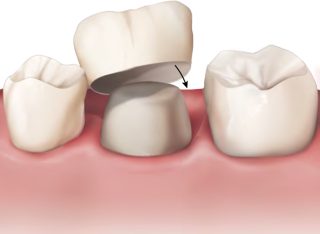

Couronne